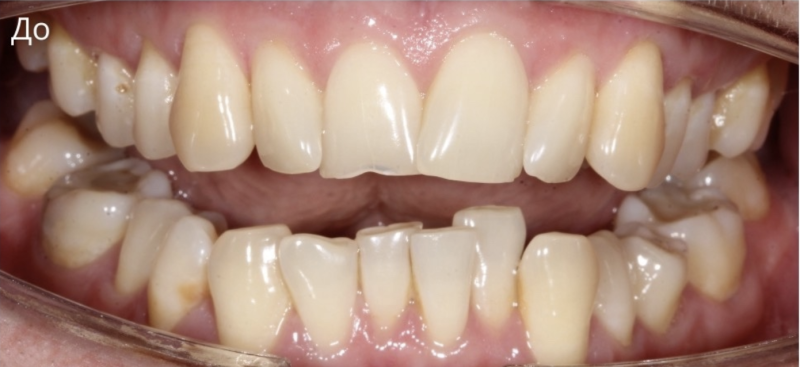

Пациентка обратилась с жалобами на сильно выраженную скученность резцов нижнего зубного ряда. Также в ходе ортодонтического лечения 6-й зуб справа на верхней челюсти ортодонтическим способом «утопили» в костную ткань, поскольку зуб вышел из окклюзионной плоскости. Тем самым значительно уменьшилось оголение шейки зуба. Продолжительность лечения 1 год, сапфировые брекеты.

Доктор: Хачатрян Лариса Рубеновна